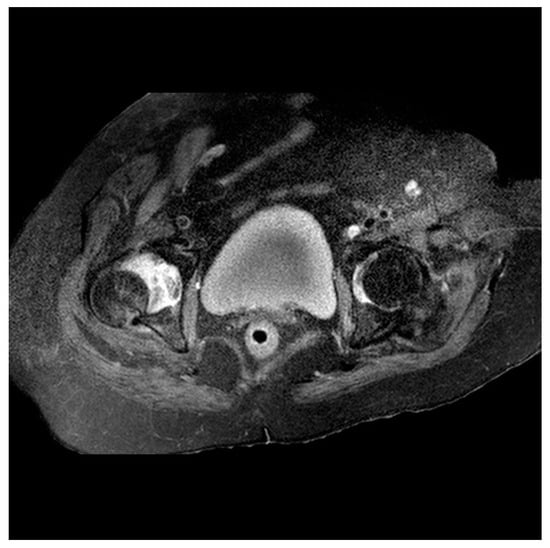

2. Case Presentation

2.1. Two-Stage Open Reduction